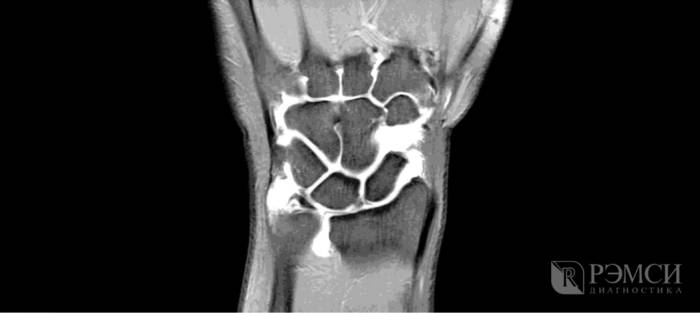

Посещения врача требуют все ситуации, кроме мышечных спазмов. В зависимости от симптомов и показаний, вам могут назначить самые разнообразные обследования:

• рентген запястья при травмах;

• УЗИ, МРТ или КТ при заболеваниях сустава;

• анализ синовиальной жидкости при артрите, остеоартрозе и тендините.

image

Благодаря этим исследованиям можно будет точно выяснить причину боли, уровень повреждения костей и мягких тканей, наличие заражения или некроза. Если при первом осмотре доктор не сможет сразу определить причину боли, то он назначит и рентген, и анализы крови. А по первым результатам уже будет понятно, как продолжать осмотр и начать лечение.